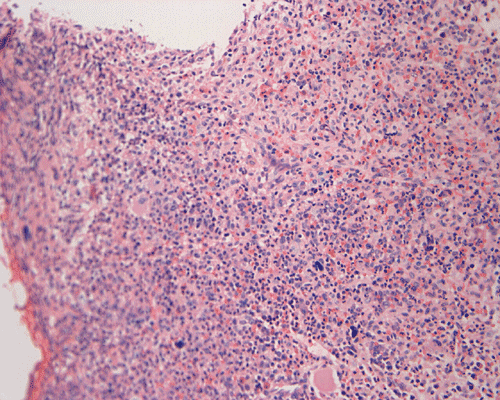

Clinical information The patient was a 73 year-old man with an itchy skin rash, hepatosplenomegaly, and gastrointestinal bleeding.  On admission, his complete blood count (CBC) showed an elevated white count (21,000/cm3) with 25% monocytes and 16% eosinophils, hemoglobin of 9.8 g/dL and 8,000 platelets/cm3.  His 24-hour urine histamine was >200 mg/mL (ref 5.6-13.5 mg/mL). A bone marrow biopsy was performed and the representative photomicrographs are illustrated below:

Since increased mast cells can be seen in a variety of benign and reactive conditions in the bone marrow. The key morphological features indicating non-reactive, clonal proliferation of mast cells are the abnormal aggregation of mast cells in bone marrow or extracutaneous sites and/or the recognition of atypical mast cells.  Mast cell disease should be considered in the differential of cases characterized by extensive myelofibrosis and may be found in a perivascular or trabecular arrangement. As the histological findings can be subtle, knowledge of appropriate clinical information and a high index of suspicion is necessary to identify mastocytosis.

Normal mast cells have a round or oval, centrally located nucleus with uniform distribution of dark purple granules in the cytoplasm.  Mast cells are well demonstrated by toludine blue and Giemsa stains, and also by immunohistochemistry for CD 117 or tryptase. Napthol ASD chloracetate esterase also highlight mast cells specifically. Mast cells are also positive for CD45, CD33, and CD68 but these markers are less specific than tryptase.  Bone marrow aspirations stained with Giemsa are most useful for recognizing atypia in mast cells. It should, however, note that Giemsa stain may be false negative in formalin fided tissue. Hallmarks of atypia in mast cells include spindling of mast cells, hypogranulation, uneven granule distribution, and nuclear lobulation.  Recognition of the so-called mast cell granuloma, in which mast cell aggregrates are associated with lymphocytes and eosinophils can be helpful.

In the bone marrow, three morphologic patterns of mast cell accumulation have been recognized.  Type I shows focal clusters of mast cells with preservation of bone marrow fat and other hematopoetic elements.  The burden of mast cells is more in Type II and usually shows patchy clusters of mast cell replacing bone marrow in a hypercellular marrow background with osteosclerosis and fibrosis.  Type III is diffuse replacement of the marrow space with mast cells, often with circulating mast cells in peripheral blood.  It is also important to note that mast cells are easily over looked on routine H and E stain or are mistaken for histiocytes.